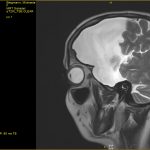

Für diejenigen von Euch, die es auch immer wieder mal interessiert wie es in meinem Kopf aussieht, habe ich hier zum einen mal drei der vielen Bilder von gestern

Außerdem gibt es die Möglichkeit mal eine kurze „Durchreise“ durch meinen Kopf zu machen. Dafür habe ich Euch hier mal zwei Screeningsfrequenzen von gestern hochgeladen. Einmal Frontal und einmal seitlich. Bei der Frontalsequenz ist es so als ob ihr quasi von vorne durch mein Gesicht nach hinten durchschaut. Deshalb ist mein Untermieter somit auf der rechten Seite in den Aufnahmen zu sehen (eigentlich nicht zu übersehen so groß und in dem Fall schwarz er auf den Aufnahmen ist). Bei der Seitensequenz schaut ihr quasi von der linken Seite meines Kopfes hindurch bis zur rechten. Sozusagen so, als ob ihr mir von meiner linken Schulter kommend hindurch bis zur rechten Schulter durchläuft. Da die Aufnahmen von der linken Seite her kommend sind läuft ihr quasi direkt im Untermieter beginnend los und deshalb habt ihr da erst mal dann in voller Größe eine schwarze Fläche an Untermieter bevor die ungefähr Höhe Nase in einen „normalen Bereich“ wo dann im kompletten Schädel Hirnmasse zu sehen ist – meiner rechten Hirnhälfte – durchläuft.

Tja das sind nun wenige Teile der gestern neu gemachten Aufnahmen. Ich denke unschwer zu erkennen, dass mein Untermieter sich nach wie vor in voller Pracht präsentiert. Auch der Doc meinte gestern so, dass es immer wieder erstaunlich wäre. Er selbst hätte in seiner ganzen Karriere noch nie einen Untermieter solchen Ausmaßes gesehen. Ich bin mir sicher, der wird mich in seinem ganzen Leben nie vergessen. ![]()